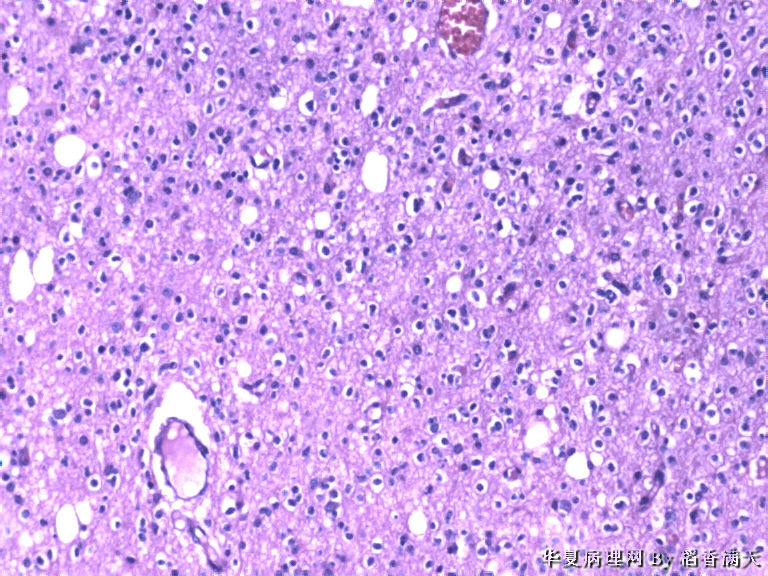

患者,女,39岁,发现左额叶占位1天入院,MRI示左额叶占位,术中见肿块约2*2cm,乳白色,包块质韧。

• 左额叶占位图3

图3

少突胶质细胞瘤

favor oligo.